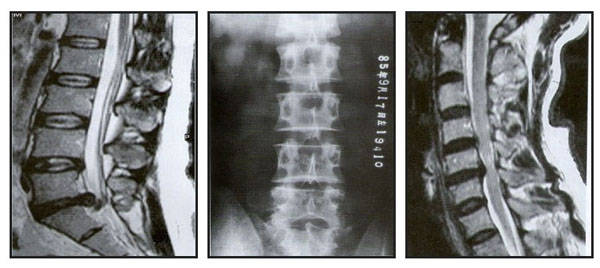

骨刺

坐骨神經痛

椎間盤突出

頸椎椎間盤突出

腰椎間盤突出

1.頸椎:頸肩酸痛,手麻痺無力,頭暈頭痛,頸椎退化

,頸椎間盤

突出

2.腰椎:腰背酸痛,臀部酸痛,腿酸痛麻痺,坐骨神經痛,腰椎退化

,

腰椎間盤

, 移位.